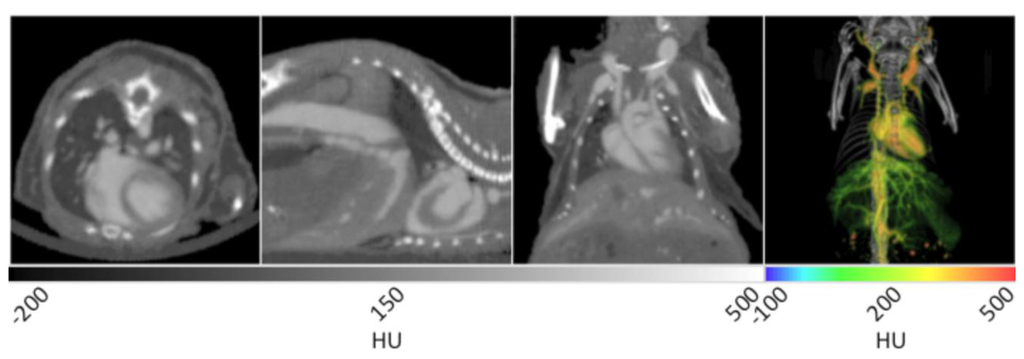

The use of AuroVist™ enabled the imaging of vasculature within a number of organ systems when injected IV into a mouse (strain SKH1, male, 6 weeks old). As noted in Figure 4, major components of the cardiovascular system including the heart, carotid arteries, aorta, and hepatic vasculature are highlighted by the presence of the contrast agent. AuroVist™ provided adequate contrast enhancement of the heart to enable the visualization of even more detailed structures within it, including the aortic arch and individual chambers. In addition to the major components of the cardiovascular system, AuroVist™ also enabled the imaging of liver and renal vasculature, the iliac and femoral arteries, and the male reproductive organs (data not shown). In the first panel of Figure 4, the heart is clearly enhanced while the heart wall is visible as an area of darker contrast. In addition, an increase in contrast of the pulmonary vasculature was noted in the lungs. In the second panel from the left, the abdominal aorta, heart, heart wall, and a small amount of hepatic vasculature are highlighted by the AuNP. In the third panel, the heart, aortic arch, and carotid arteries are visible. The slice data in Figure 4 may be used to directly measure the diameter (µm) of vasculature at various anatomical locations, and also inspect for structural abnormalities. Unlike the figures illustrating natural lung tissue, adipose tissue, and brain tissue contrast, a VOI was drawn around vasculature and used to mask the surrounding skeletal structures. Once the skeletal structures with similarly high attenuation values were masked, the resulting image was then analyzed while retaining the original attenuation values for each voxel. The masked vascular data were given a rainbow intensity scale and overlaid on the original CT data to yield a 3D visualization of the mouse, given in the right panel of Figure 4. This 3D rendering shows all the previous structures in addition to extensive hepatic, spleen, and kidney vasculature. Quantitative data can be obtained for various regions of the vasculature through a ROI or VOI analysis of HU attenuation values in a given area. If a pre-injection CT image is obtained, it can serve as a control to determine the amount of contrast enhancement after various doses and time points.